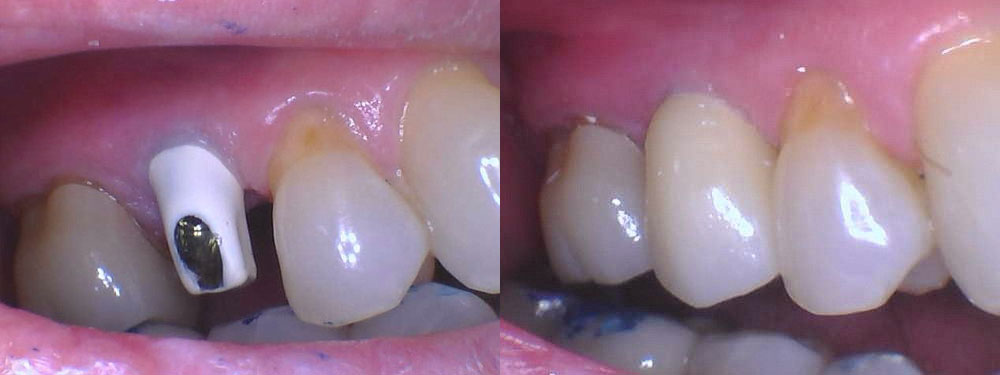

- Natural Appearance: Dental implants blend seamlessly with your natural teeth, providing a lifelike restoration that enhances your smile.

- Implant Placement: The dental implant placement procedure is performed under local anesthesia for your comfort. Dr. Cordora will carefully place the titanium implant posts into the jawbone at precise angles and depths to ensure the stability and strength of each implant.

- Final Restoration: Once the implants have fully healed and integrated with the jawbone, custom-made dental crowns, bridges, or dentures are securely attached to the implants, completing your smile restoration.